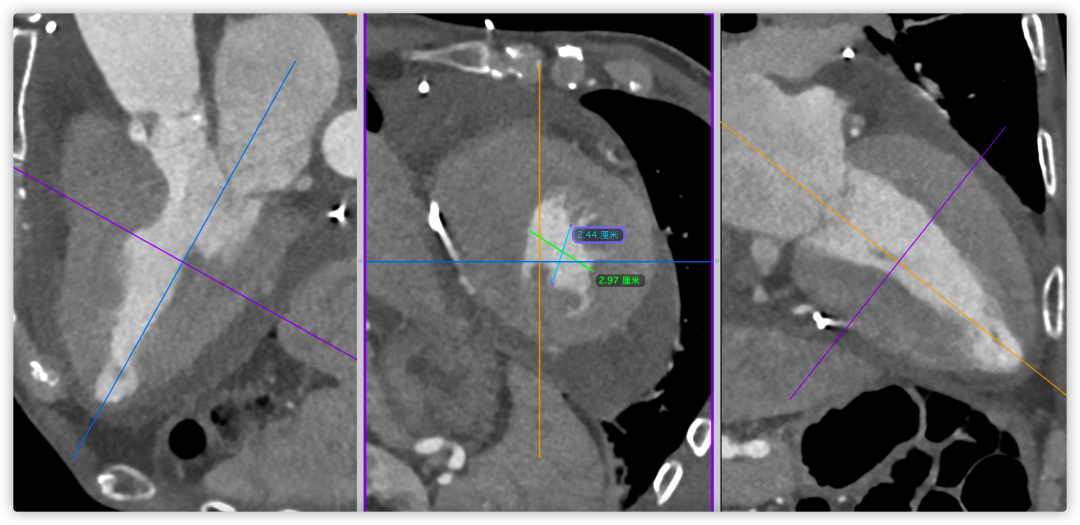

主动脉根部CT断层

根部角度/瓣环/左室流出道

SOV/STJ/AAO

左冠风险评估